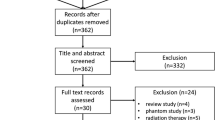

Exclusion criteria were male patients, history of allergic reaction to contrast agents, renal insufficiency, pregnancy and women aged less than 40 years (Fig. 1).